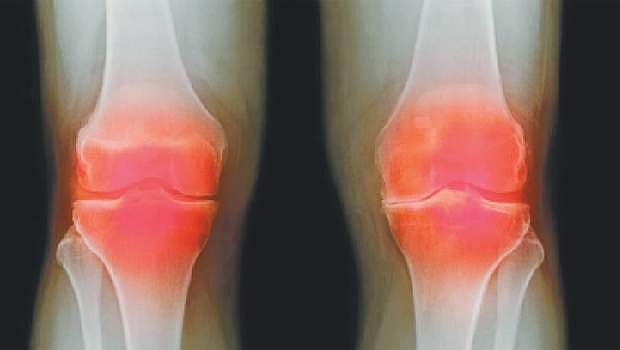

ஆயுள் காக்கும் ஆயுர்வேதம்: மூட்டுத் தேய்மானத்தைச் சரி செய்ய...!

எனது மனைவிக்கு 73 வயதாகிறது. நடக்க முடியாமல் மிகவும் கஷ்டப்படுகிறார். மூட்டுத் தேய்மானம் உள்ளது.

எனது மனைவிக்கு 73 வயதாகிறது. நடக்க முடியாமல் மிகவும் கஷ்டப்படுகிறார். மூட்டுத் தேய்மானம் உள்ளது. முடிந்தவரை நடக்கட்டும். முடியாமல் போனால் அறுவை சிகிச்சை செய்து கொள்ளலாம் என மூட்டுவலி டாக்டர் கூறிவிட்டார். இதற்கு ஆயுர்வேத மருந்துவம் உள்ளதா?

மூட்டுப் பகுதியில் எலும்புகளுக்கிடையிலான உராய்வு ஏற்படாமலிருக்கவும், "சிலேஷகம்' என்ற ஒரு கபம் அவ்விடத்தில் வழுவழுப்பை ஏற்படுத்தி, பாதுகாப்பான அரணாக விளங்குகிறது. வயோதிகத்தில், உணவினுடைய செரிமான விசேஷத்தினால் இப்பகுதிக்கு வர வேண்டிய ஊட்டச் சத்தான குணங்களாகிய நெய்ப்பு, கனம், மந்தம், வழவழப்பு போன்றவை வராமல் போவதால் தான்... இந்த சிலேஷகம் என்ற கபம் தன் செயல்திறன் குன்றி, வாயுவினுடைய குணங்களாகிய வறட்சி, லேசு, குளிர்ச்சி, சொர சொரப்பு ஆகியவற்றிற்கு வழி விடுவதால், மூட்டுத் தேய்மானம் ஏற்படுகிறது.